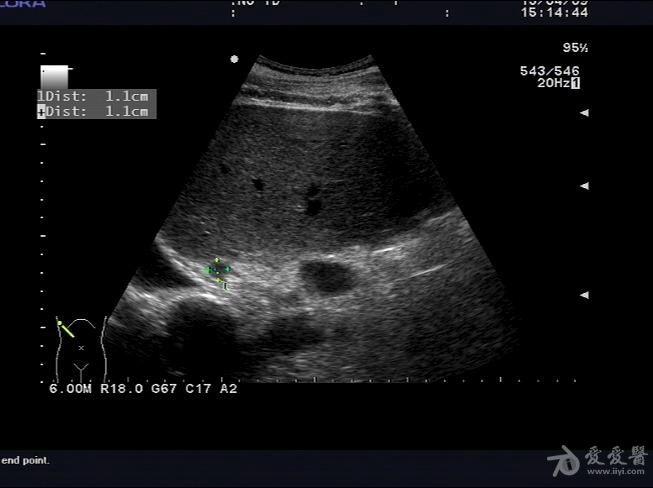

肾上腺彩超

肾上腺彩超,肾上腺正常

肾上腺超声

肾上腺正常解剖及疾病超声诊断

肾上腺病变大家讨论 - 超声医学讨论版 - 爱爱医医学论坛-爱爱医医学

超声诊断肾上腺转移ca声像图表现zengerya